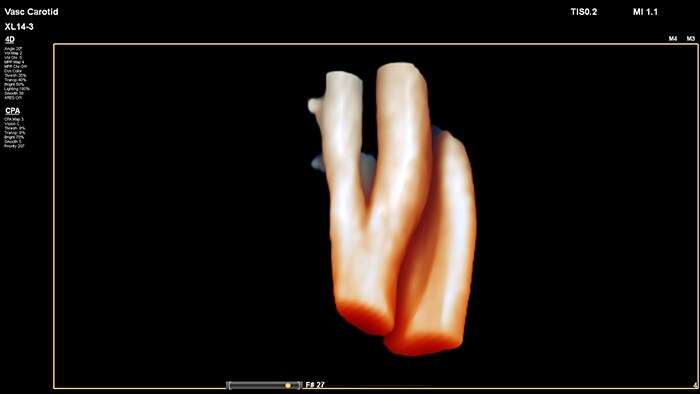

Función 3D/4D sencilla

Asimismo, el XL14-3 tiene capacidad para visualizar la anatomía en asombrosas imágenes 3D/4D mediante un flujo de trabajo sencillo mediante iconos. Los profesionales clínicos pueden ver el interior de un vaso sanguíneo directamente para evaluar la composición y la ubicación espacial de las placas, además de los datos del flujo 3D para estudiar las anomalías relacionadas con la estenosis o la tortuosidad.

La interfaz de usuario 3D/4D también permite generar un modelo de vaso sanguíneo mediante los datos del flujo. El modelado de vasos sanguíneos 3D permite visualizar el flujo de manera directa para realizar un análisis en profundidad de la estenosis o de anomalías relacionadas con la tortuosidad. La ventaja principal: la visualización 3D/4D de la anatomía vascular ofrece una herramienta de comunicación idónea para facilitar las decisiones clínicas entre los proveedores, y también para mejorar las consultas con los pacientes con el fin de ayudarles a comprender su enfermedad.